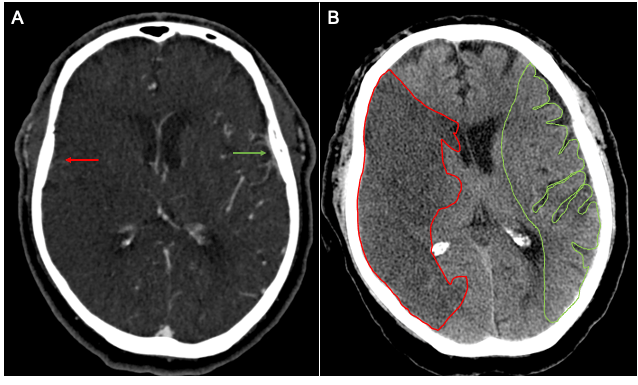

Venous Outflow Profiles Are Linked to Cerebral Edema Formation at Noncontrast Head CT after Treatment in Acute Ischemic Stroke Regardless of Collateral Vessel Status at CT Angiography

Faizy T, et al. (2021) Radiology Apr 6;203651. doi: 10.1148/radiol.2021203651. Online ahead of print.

Favorable Venous Outflow Profiles Correlate With Favorable Tissue-Level Collaterals and Clinical Outcome

Faizy T, et al. (2021) Stroke Mar 8;STROKEAHA120032242.

doi: 10.1161/STROKEAHA.120.032242.Online ahead of print.